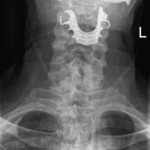

The man went to the emergency room because he was having a hard time swallowing and was coughing up blood. Doctors ordered a chest X-ray, diagnosed him with pneumonia and sent him home with antibiotics and steroids. It took another hospital visit before another X-ray revealed the problem: His dentures — a metal roof plate and three false teeth — lodged at the top of this throat.